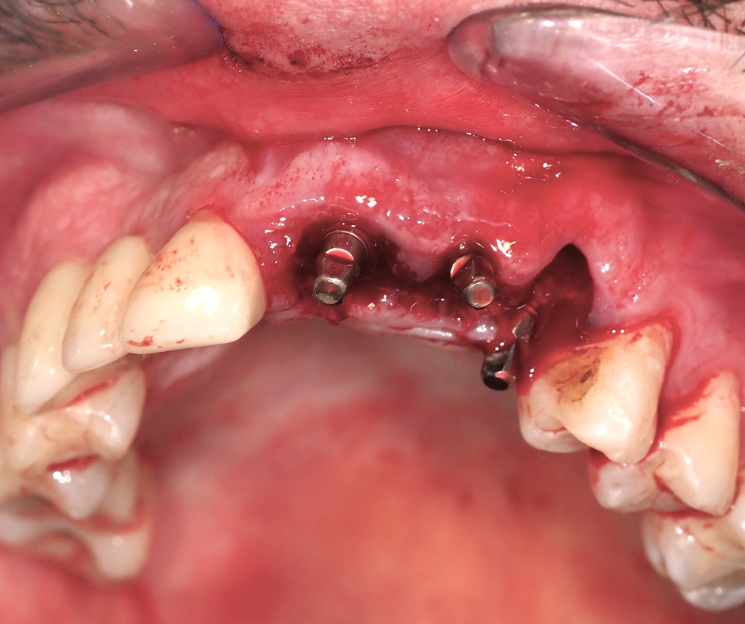

Extracción de piezas 21, 22 y 23 con infección activa

Paciente con infecciones de origen dental que comprometían severamente el hueso alveolar en la zona anterior superior. Se realizó la extracción de los dientes 21, 22 y 23, y se optó por una rehabilitación inmediata mediante implantes córticobasales.

Esta combinación permitió anclar los implantes en hueso cortical, que mantiene su estabilidad incluso en presencia de procesos infecciosos en el hueso alveolar. El resultado: rehabilitación funcional y estética el mismo día de la cirugía.